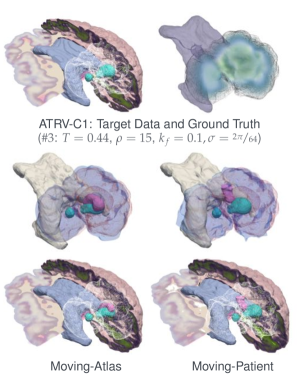

Notice that the main difference is switching the order of the registration and the tumor operators; see Fig. 1 for an illustration. This seemingly simple change has significant impact in the solution of this problem. In [49, 48], we used the Moving-Patient scheme and only inverted for the tumor initial condition. Note that in MP, to evaluate the objective function, we first grow a tumor in the atlas and then deform the patient image to match the resulting tumor-bearing atlas. As long as the tumor-bearing atlas is topologically similar to the tumor-bearing patient brain, image registration can always yield good tumor reconstruction, even with completely wrong tumor parameters. Thus this approach enables efficient non-diffeomorphic registration between an atlas and a tumor-bearing patient, but is limited in terms of meaningful tumor inversion.

In this paper, we propose the Moving Atlas scheme. To evaluate the objective function given, we first deform the healthy atlas (using ) so that it matches the patient. Then we grow a tumor in the transformed atlas. It turns out that the new formulation is more appropriate for the biophysical modeling since the tumor growth takes place in images that resemble the actual patient.

Purpose. This case is designed to cause the Moving Patient scheme to fail due to large differences in the brain anatomy between patient and atlas in the tumor region. We demonstrate that the Moving Atlas scheme retains good reconstruction quality for the tumor anatomy label, the tumor initial condition, and the characteristic diffusivity of tumor cells, while the Moving Patient scheme falls short as it inverts tumor growth in the ’wrong’ (atlas) geometry.

Setup. For both, atlas and patient, we generate a purely synthetic brain anatomy, composed of an elliptical white matter inclusion surrounded by gray matter. The white matter inclusions for atlas and patient differ greatly in size. The target data are generated synthetically from a tumor-progression simulation (with ) using our reaction-diffusion model with and from an initial condition with two nearby Gaussians enabled in the patient geometry. The healthy atlas geometry is depicted in the first row, the tumor bearing patient geometry in the last row of Fig. 2. We use the same set of Gaussians with standard deviation for the target data generation and inversion. For simplicity, tumor growth is enabled only in white matter. We invert for the registration velocity , the parameters for the tumor initial condition, and for the characteristic diffusivity in white matter.

Observation. In this case, the inclusions of white matter in atlas and patient vary significantly in size (cf. Fig. 2). Thus, registering the atlas to the patient requires strong local expansion of volume. Looking at Fig. 2 (right tableau), in the first iteration, to prevent the registration from directly matching the target tumor unaided by the tumor solver, we choose a higher regularization parameter for the registration problem. Therefore, warping the target tumor to the atlas space basically corresponds to a copy operation. (before ). This warped-to-atlas tumor is used for tumor inversion in the atlas space. The subsequent registration step (with lower regularization) computes a velocity that registers the patient (small tumor in large white matter blob) to the atlas (small tumor in small white matter blob). This results in a compression of the patient white matter, and consequently yields a very small target tumor for the inversion in the atlas ().151515Note, the displayed results are in the patient space, i.e., the inverse of the deformation is applied to display atlas labels in patient space, and the very small reconstructed tumor in the atlas is expanded when warped to the patient space. In subsequent iterations (with further reduced registration regularization), the warped-to-atlas target tumor is compressed further, ultimately causing the Moving Patient scheme to fail and returning a relative error of almost for the reconstruction of the tumor label, the reconstruction of the tumor initial condition, and the reconstruction of the characteristic diffusivity in white matter cf. Fig. 2). The new Moving Atlas scheme, however, maintains a good reconstruction quality and results in only relative errors for the tumor label, relative errors for the reconstruction of the tumor initial condition and relative error in the reconstruction of the characteristic diffusivity rate in white matter.